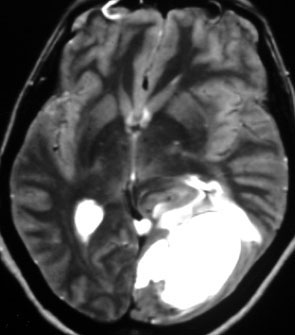

40代女性の後頭部傍矢状洞部の硬膜に発生したグレード3です。腫瘍周囲の強い浮腫のために,頭頂葉のゲルストマン症候で発症しました。術前診断は髄膜腫でしたが,腫瘍内部にのう胞(液体が溜まっている)があり,髄膜腫としては典型的な画像ではありません。右側の血管撮影にみられるように,上矢状洞が一部狭窄して腫瘍が浸潤している所見があり,腫瘍が濃染します。腫瘍の周囲の脳には出血がありました。大脳鎌と上矢状洞の壁を含めて全摘出しました。